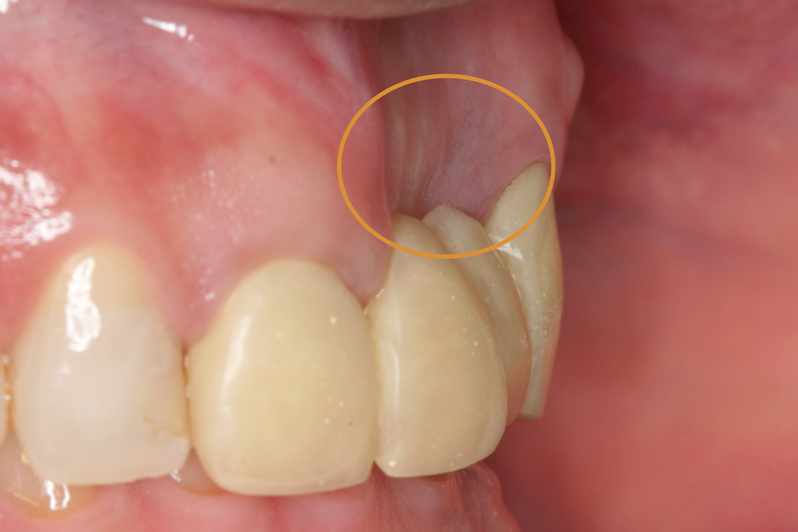

23.自然な形態のインプラント歯頚部

適切な治療計画と治療技術を有することで、このような自然な形態のインプラント歯頚部を形成することができます。